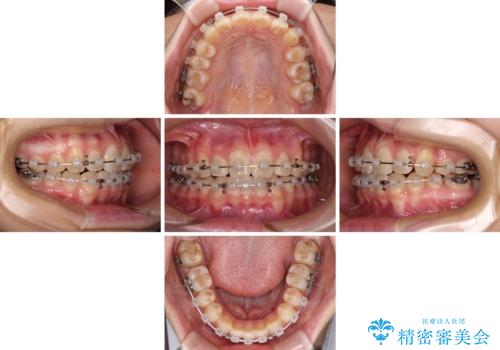

まずは補助装置を用いて八重歯を改善し、インビザラインにて歯列を整えましたが、当初の懸念が的中し、臼歯部の咬合を安定させることができませんでした。

海外留学の予定もあったため、後半は上下ワイヤー装置にて矯正治療を継続し、違和感なく咬合させることとなりました。